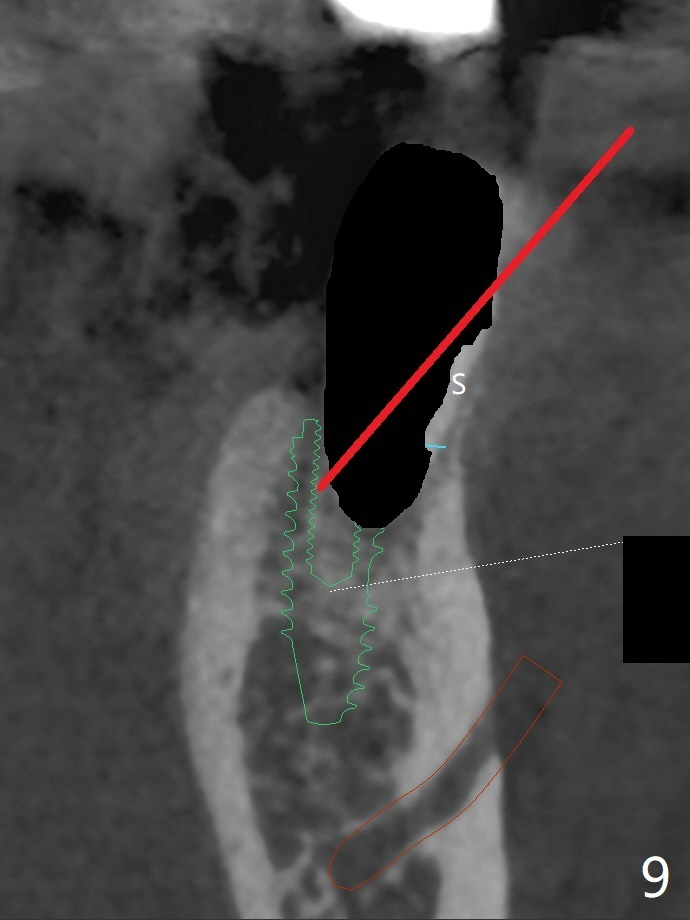

Re-analysis of preop CT reveals extensive bone loss around #18 (Fig.1 (lingual view)). Blood is withdrawn for sticky bone. After implant placement (Fig.2), sticky bone is placed at #18 (Fig.3 red dashed line (yellow: superior border of the Inferior Alveolar Canal)). PRF membrane and an immediate provisional FPD (#18-20) further keep the bone graft in place for healing. Four months postop, the patient reports difficulty in mastication on the left and requests extraction of the tooth #20 for implant (Fig.4). The implant will be placed lingually, while socket shield will be performed buccally (Fig.5 S) to keep bone graft in place. The implant at #19 is equicrestal (Fig.6); the one at #18 is apparently supracrestal buccally (Fig.7). Since there is a lot of scattering from nearby crowns, the implant at #20 will be placed free hand. To overcome the thick dense lingual plate (Fig.8 L), osteotomy is initiated (Fig.9 red line) in the middle of the lingual wall of the extraction socket (black area) on the top of the socket shield (S). After the last drill (3.5x11.5 mm, Fig.10 pink) and before 4x11.5 mm implant, use Lindamann bur to remove the coronal portion of the lingual plate (Fig.11 red line) to prevent implant buccal deviation.